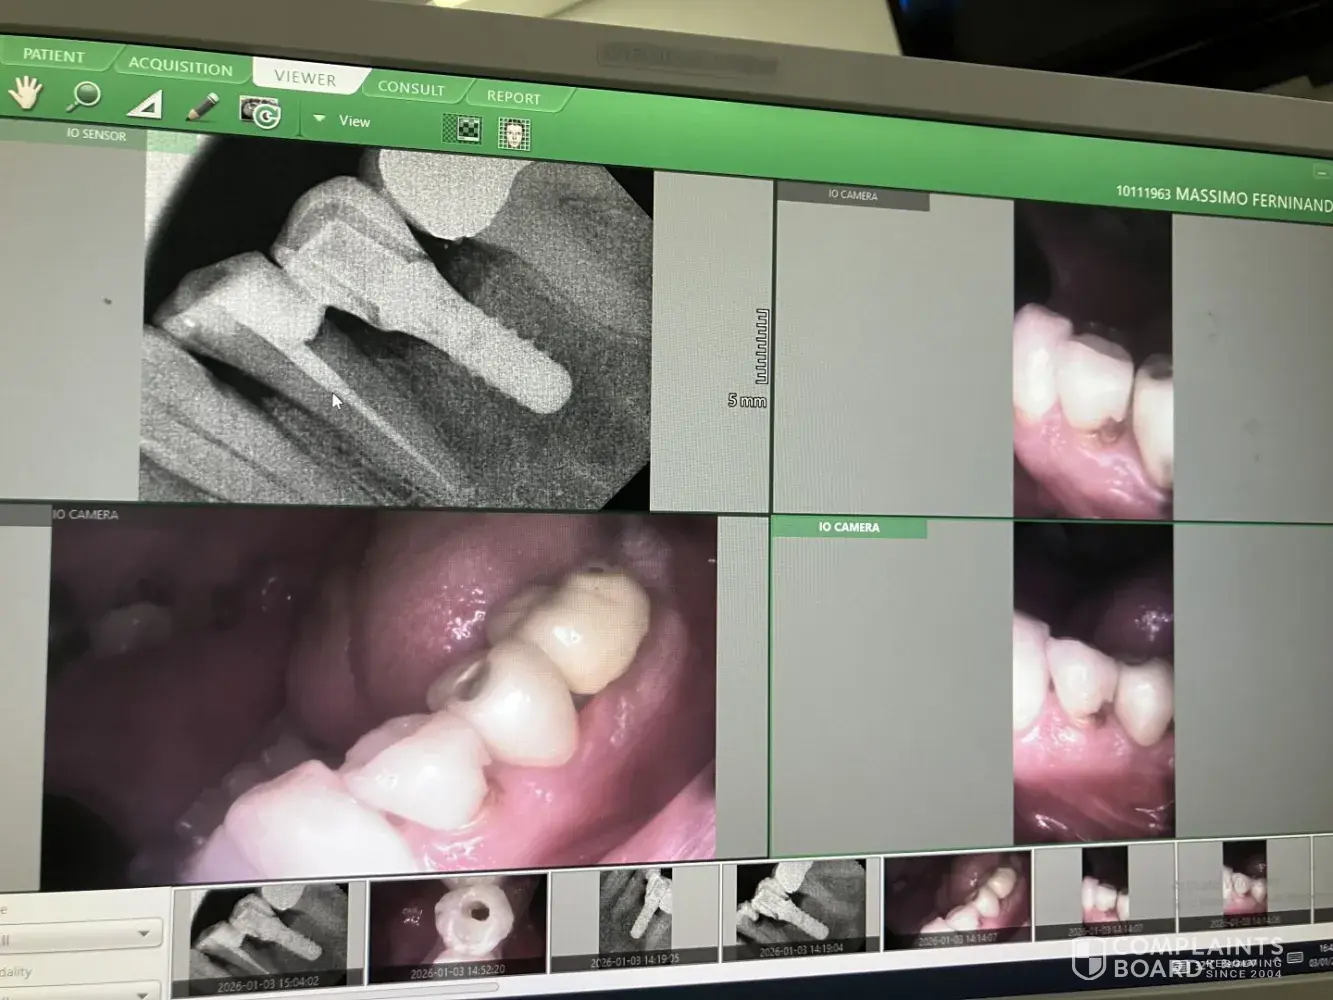

Q & M Dental Group Terrible!!! Incredible mistake!!!

Totally wrong diagnosis! Luckily I contacted my dentist in Italy. I was feeling pain in the lower left part and he Q&M dentist found the cause in the top left part suggesting extraction or root canal. He made panoramic xray and checked all my tooth one by one and didn’t see an obvious cavity in the bottom left. Please check the attached photo! My Italian...